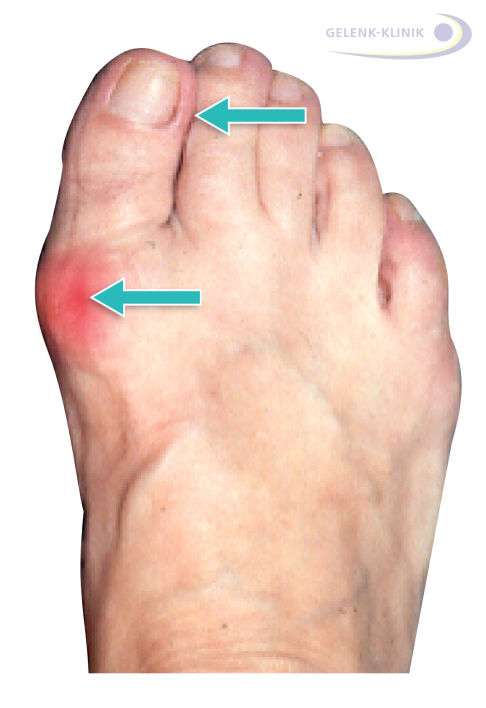

Der Hallux valgus wird auch als Ballenzeh oder Schiefzehe bezeichnet und ist eine besonders bei Frauen weit verbreitete Fehlstellung der Großzehe. Der große Zeh weicht dabei auffällig zum Fußaußenrand hin ab und verdrängt dort die kleineren Zehen. Diese Fehlstellung überlastet das Großzehengrundgelenk, wodurch als Folge langfristig eine schmerzhafte Arthrose der Großzehe (Hallux rigidus) entstehen kann.

- Der hervortretende Fußballen am Großzehengrundgelenk entzündet sich schmerzhaft und kann anschwellen.

- Der große Zeh zeigt nicht mehr gerade nach vorne, sondern in Richtung der kleinen Zehen. Er drückt diese zusammen und verursacht oft Schwielen und Hautirritationen.

- Am Großzehengrundgelenk bildet sich häufig Hornhaut durch den Konflikt mit Schuhen an der Stelle des Überbeins (Exostose). In vielen Fällen begleitet eine Schleimbeutelentzündung (Bursitis) am Zehenballen den Hallux valgus und verstärkt die Problematik.